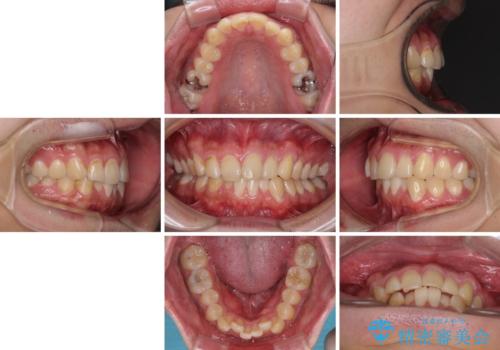

- 上下前歯のデコボコを気にして来院された患者様です。

前歯のデコボコ以外に左側の奥歯の咬み合わせに問題がありましたが、価格を抑え、短期間で気になる前歯を治したいとのことでした。

こちらの患者様は、事前のシミュレーションにより、インビザライン・ライトでは前歯のデコボコを解消しきれないことが分かったため、通常のインビザライン(コンプリヘンシブパッケージ)での治療が必要となりました。

しかし、費用面や期間で悩んでいらっしゃったため、左側臼歯の問題は解決せずに前歯のデコボコのみを改善するシミュレーションを作成し、治療を行うこととしました。